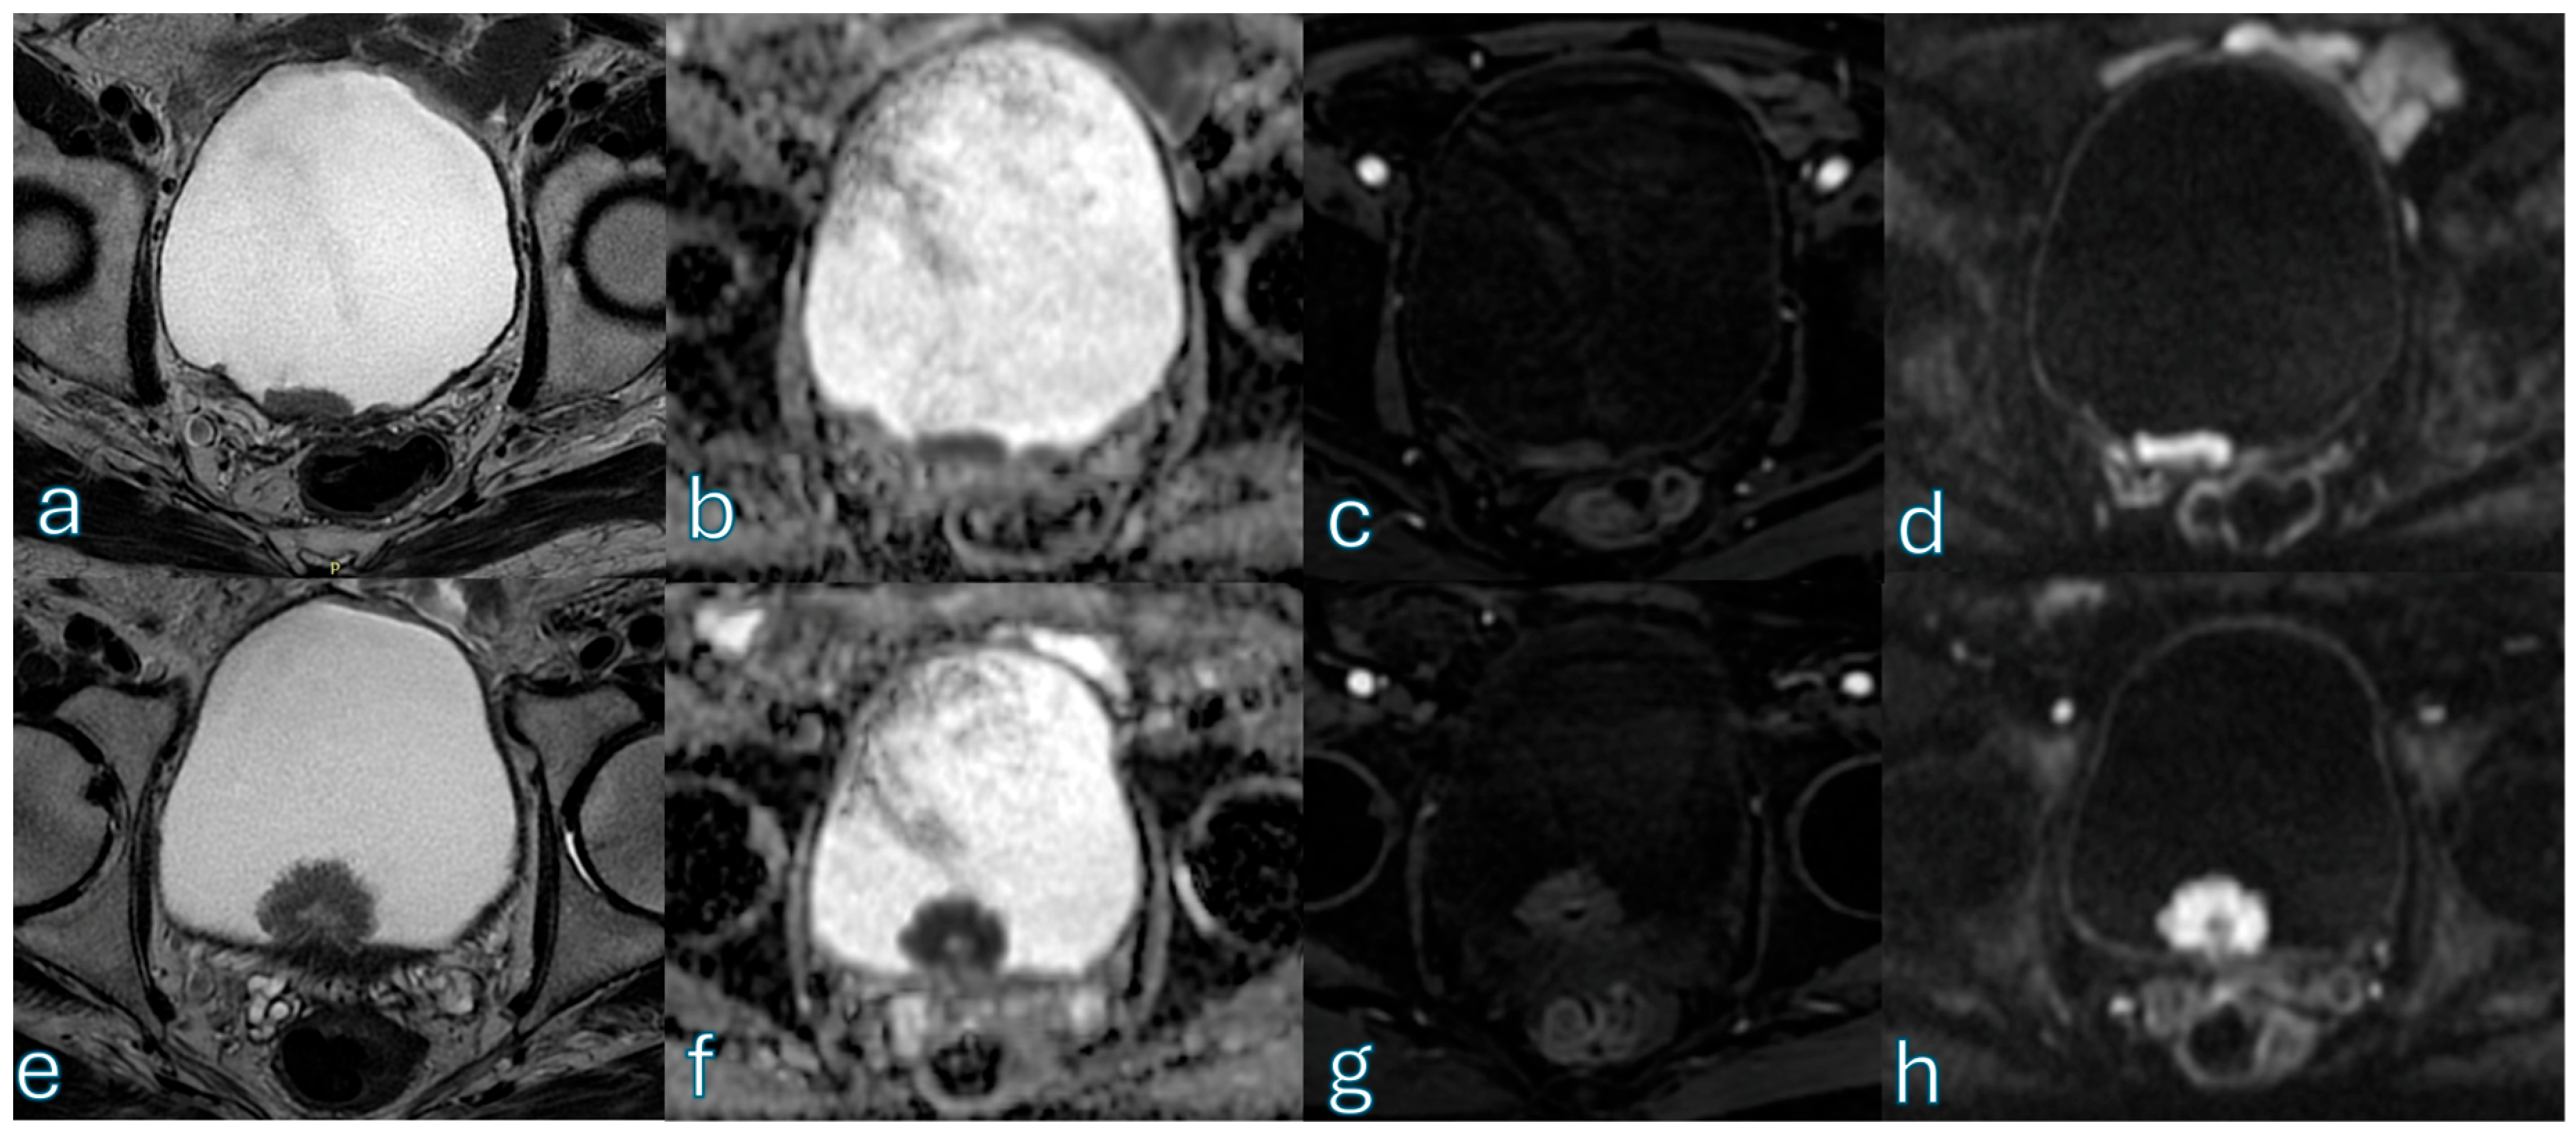

3.5. Agreement Analysis

3.6. ROC Analysis for High-Likelihood Muscle Invasion (VI-RADS ≥ 4)